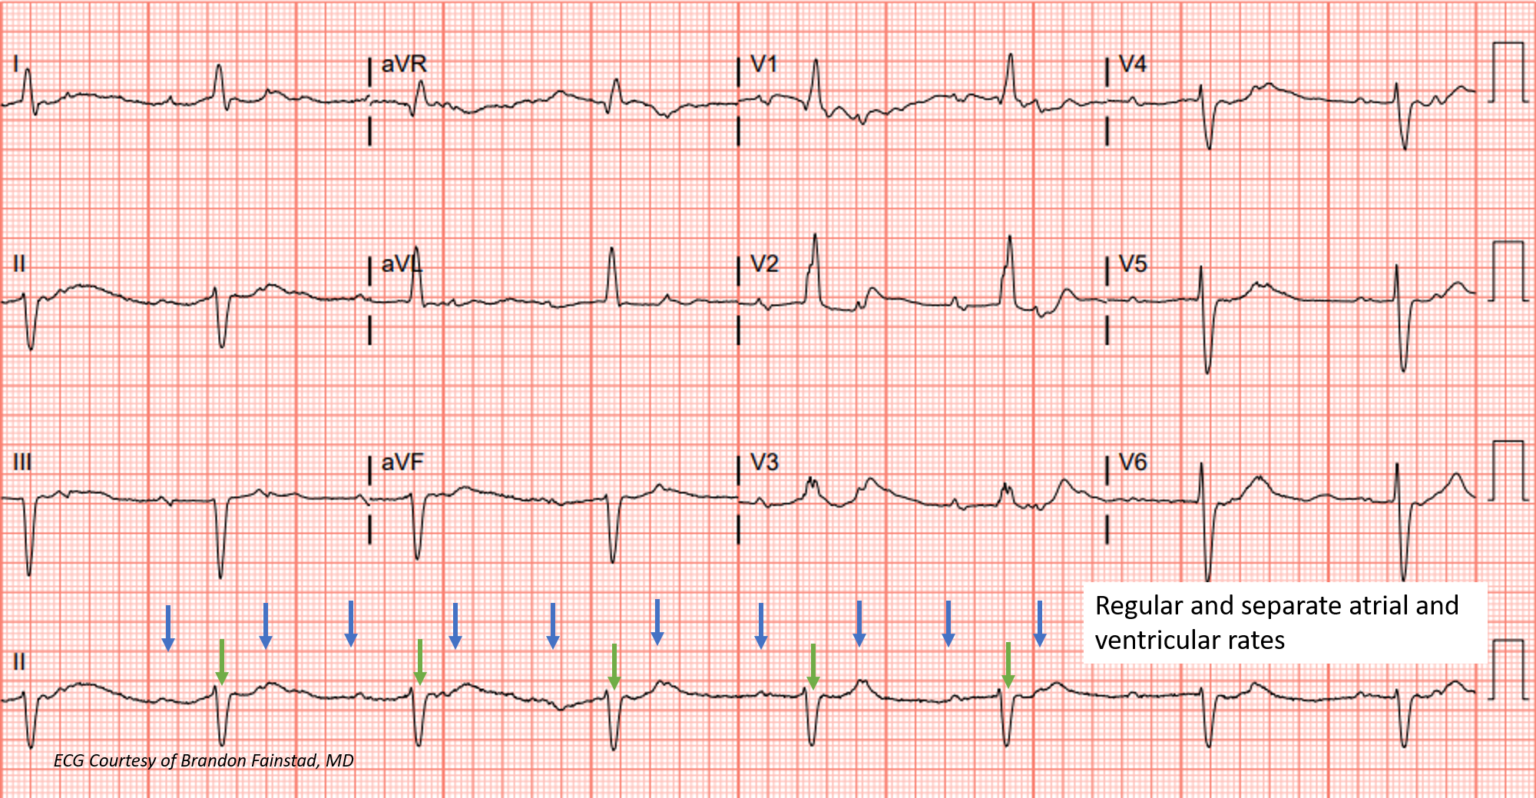

ECG Rhythms Is this Complete Heart Block? Heart Block Go Away The prevalence of left bundle branch block (lbbb) increases with advancing age in the general population. An av heart block happens when the electrical impulses are delayed or blocked as they travel between your atria (the top chambers of your. There are three degrees of heart block. Heart block is an issue with a heartbeat signal traveling from the top. Heart Block Go Away.